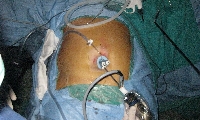

Πρόκειται για άνδρα ασθενή 46 ετών, ο οποίος υποβλήθηκε σε υπερηχογράφημα άνω κοιλίας στα πλαίσια διερεύνησης επαναλαμβανόμενων επεισοδίων επιγαστραλγίας με αντανάκλαση στη δεξιά ωμοπλάτη και τάση προς έμετο. Διαπιστώθηκε χολολιθίαση. Υποβλήθηκε σε λαπαροσκοπική χολοκυστεκτομή μονήρους οπής (SILS). Η τοποθέτηση της θύρας ενδοπεριτοναϊκής προσπέλασης έγινε, αντί στη διομφάλια, στην υπομφάλια θέση, εξαιτίας της ύπαρξης συγγενούς ομφαλικού αιμαγγειώματος (εικόνα 1). Χρησιμοποιήθηκαν εύκαμπτα λαπαροσκοπικά εργαλεία (εικόνα 1) με την τεχνική της διασταύρωσης των χειρών. Ο θόλος της χοληδόχου κύστης αναρτήθηκε στο κοιλιακό τοίχωμα με ράμμα. Πραγματοποιήθηκε πλήρης παρασκευή του τριγώνου του Calot (εικόνα 2) και κατόπιν ακολούθησε η διατομή του κυστικού πόρου και της κυστικής αρτηρίας (εικόνα 3). Η αποκόλληση της χοληδόχου κύστης διενεργήθηκε με τη χρήση hook διαθερμίας (εικόνα 4). Το παρασκεύασμα ανακτήθηκε άθικτο (εικόνα 5). Το άμεσο μετεγχειρητικό κοσμητικό αποτέλεσμα φαίνεται στην εικόνα 6. Έκτοτε ο ασθενής παραμένει ελεύθερος συμπτωμάτων.